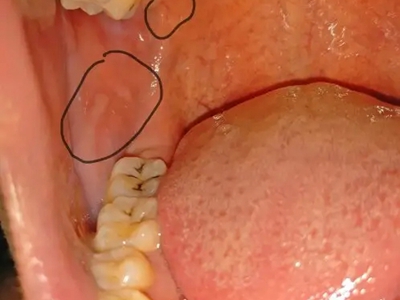

异位皮脂腺又称Fordyce病、皮脂腺异位症,为皮脂腺异位而形成,表现为黏膜上出现高于黏膜面的白色或淡黄色斑点或稍隆起的扁平斑丘疹,可聚集呈斑块样。本病以两颊黏膜及唇部黏膜多见,也可发生于外阴部位,多于青春期或青春期后发生。

皮疹为针头至粟粒大小,白色、淡黄色或黄色小斑点,或稍隆起的扁平斑丘疹,可聚集呈斑块样。当黏膜被拉紧时,皮疹表现得更明显(实际上小丘疹在黏膜内)。皮疹一般不融合,挤压皮疹并无内容物排出,有自愈的倾向,偶尔有瘙痒感或灼热感。